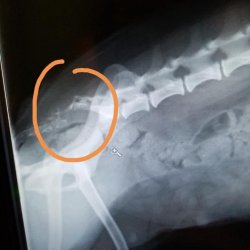

Ruby je velmi zanedbaná malá fenečka odebraná z nevhodných podmínek z Ústí. Olysalá místa na kůži měla způsobená zablešením a hormonální poruchou. Dostala speciální šampon a byla jí odebrána krev. Vzhledem k tomu, že Ruby nepoužívala ocas, který byl nehybný, zespodu odřený a ušpiněný od výkalů a moči, provedl se RTG snímek pánve, kde se ukázalo, že Ruby má ocas odtržený od pánve. Patrně po údajné autonehodě, nebo jiném úrazu v minulosti.

RTG snímek Ruby